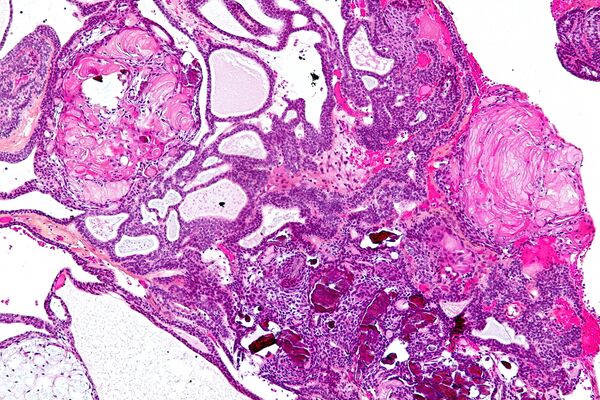

Структура краниофарингиомы с течением времени может значительно видоизменяться. В её компактных слоях происходит колликвационный некроз с формированием кист, которые содержат жидкость с большим содержанием белка (от 20 до 100 ‰ и более), кристаллов холестерина и жирных кислот. На внутренней поверхности капсулы происходит отложение солей. Гистологически краниофарингиомы состоят из эпителиальных клеток различной степени дифференциации. Выделяют адамантиматозный и папиллярный гистологические варианты строения краниофарингиомы[29]. Наряду с эпителиальными клетками эмбрионального типа встречается и эпителий эпидермального типа. Клеточные скопления в ряде случаев могут напоминать адамантиномы. Также в краниофарингиомах всегда наблюдаются дистрофические изменения различной степени выраженности в виде кистообразования, обызвествления или даже оссификации стромы. Капсула состоит из соединительной или глиальной тканей. Разнообразие в строении краниофарингиом может расцениваться как результат фазности развития новообразования[1].